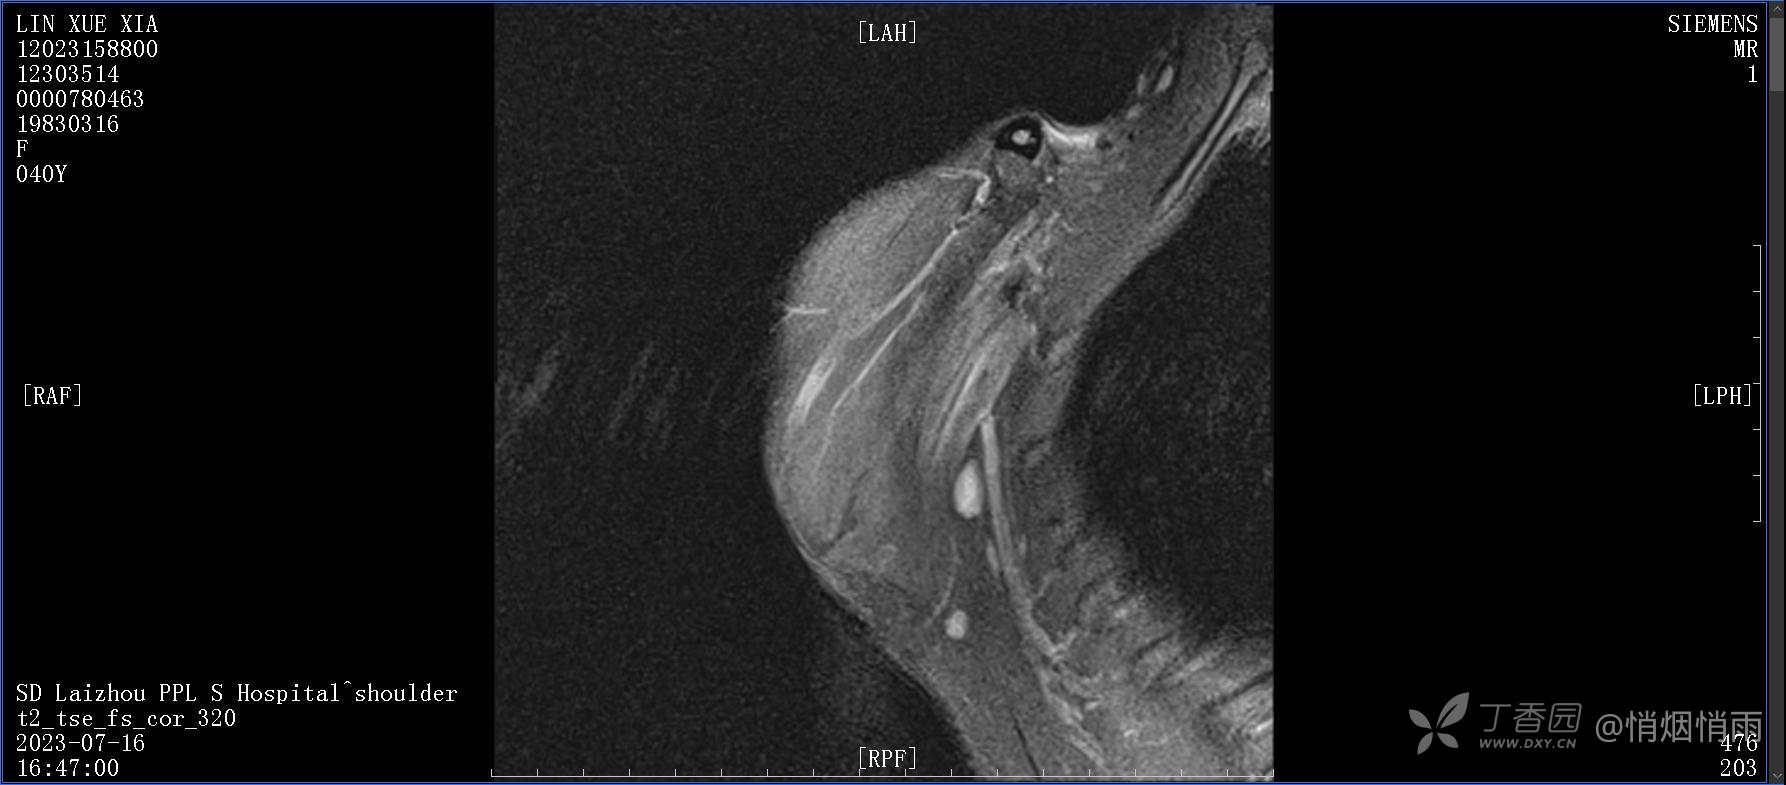

查体:右肩关节局部轻度肿胀,肩胛区压痛明显,痛处不固定,肩关节痛性活动受限,jobe test(+),lift -off test(+),中指、环指感觉较余指减退,余肢端感觉及血运情况可。

目前的诊断,暂时依据辅助检查诊为肩袖损伤,但是患者疼痛的性质和特点,却不是单纯的肩袖损伤所致。考虑过胸廓出口综合征,但是该疾病会出现肩胛区的疼痛吗?(由于考虑到费用的问题,没再进行下一步的检查)带状疱疹会有如此的症状吗?